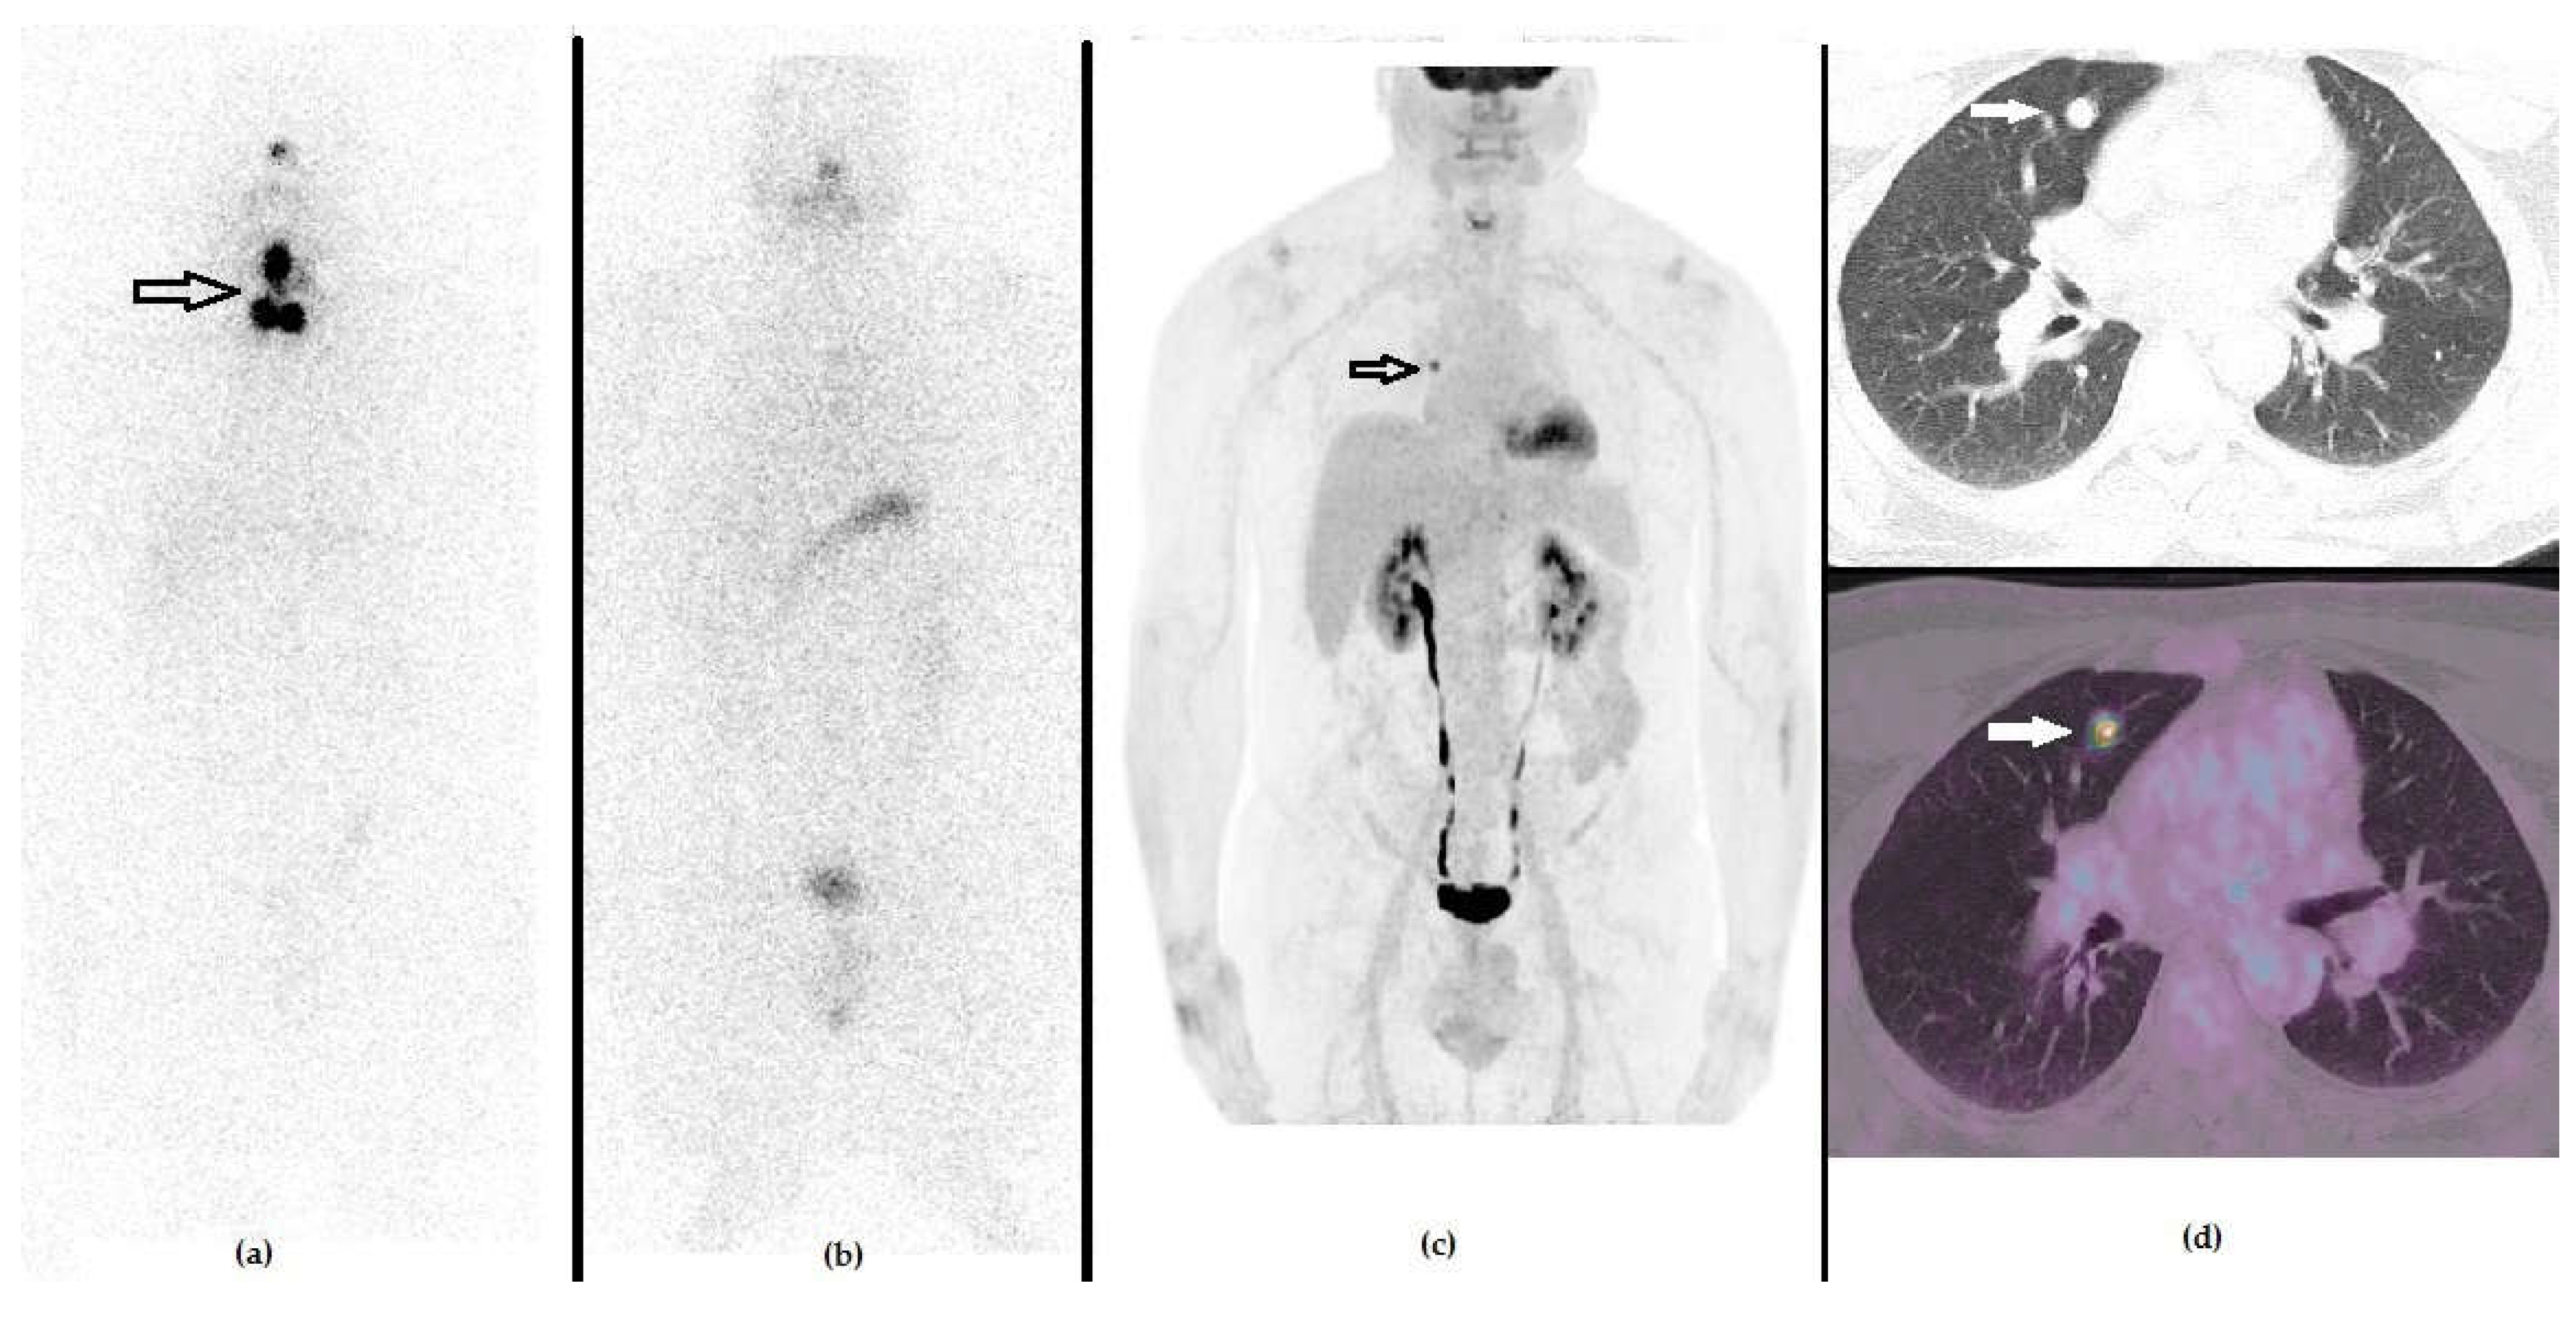

Figure 4. A 49-year-old male that previously underwent a thyroidectomy plus CND and 1 cycle of RAI due to PTC (pT3a N0 R0). The first panel represents the post-RAI 131I-WBS, showing the residual iodine-avid tissue in the anterior cervical region. (a) One year after RAI, he presented with an increased value of stimulated Tg serum level (i.e., 89 ng/mL), in spite of negative 131I-WBS (b) and no morphological signs of relapse at neck US or CXR. PET/CT with 18F-FDG demonstrated a focus of increased tracer uptake in the right lung, as evident by whole body (c) and axial CT (d, upper raw) and fused PET/CT ((d), lower raw) slices. The patient underwent surgery and histology was positive for PTC lung metastasis.